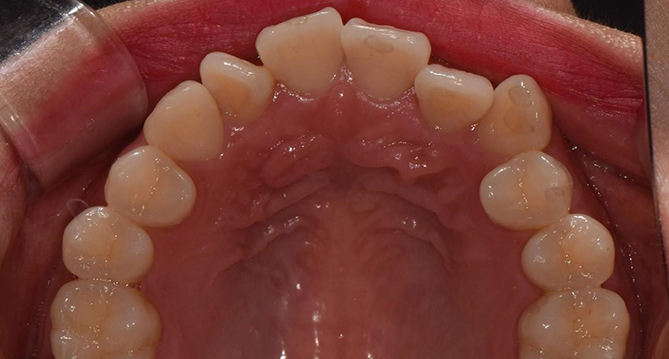

교합과 심미성을 모두 만족시키는

완벽을 추구하는 교정치료를 진행합니다.

풍부한 경험을 보유한 의료진이 직접 상담부터 유지, 치료까지 책임지고

개개인의 구강상태에 따른 적합한 최선의 치료계획을 수립하고 치료합니다.

개인의 얼굴형태나 아래위턱뼈의 형태, 성장발달 단계 등 여러가지를 고려해

치료계획을 세우는 교정은 정밀진단을 통한 올바른 치료가 중요합니다.